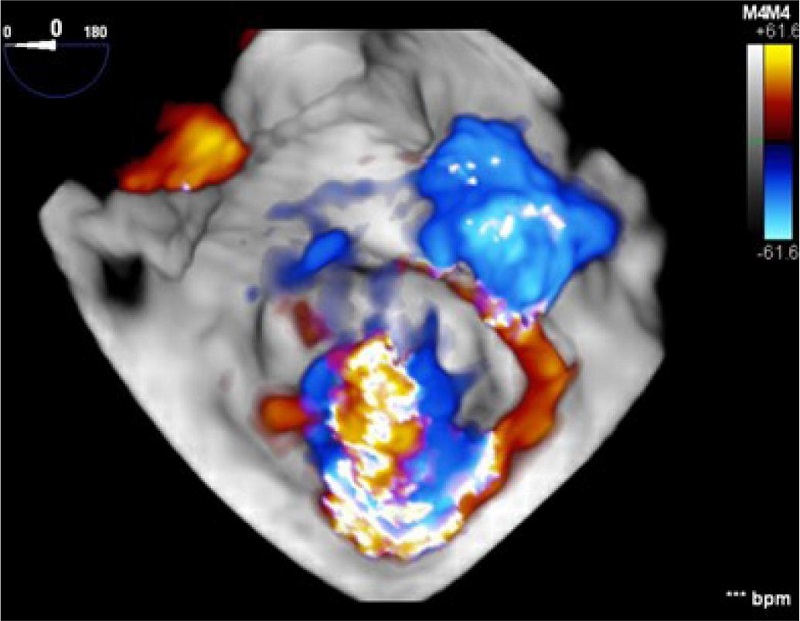

Presence of ostium secundum ASD of 14 mm with left to right shunt (Figure 2). Normal biventricular ejection fraction, enlargement of right cardiac chambers and left atrium, and noticeable MV insufficiency (Figures 3C, 4A, 4B).

MV features included annular dilation, leaflet redundancy, with failure of coaptation between A2-A3 and P2-P3, associated with multisegmental prolapsing/billowing MV components, and thickened, elongated chordae tendineae, typical of Barlow’s disease (BD) (Figures 3A, 3B, 5).